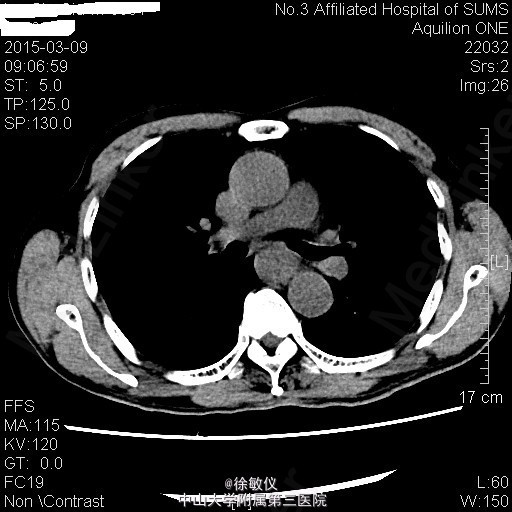

老年男性,主诉:进行性吞咽困难1月 现病史:患者1月前无明显诱因出现吞咽梗阻感,以进食粗糙、过热食物时明显,进食半流质症状不明显,10天前就诊外院行胃镜检查提示:食管癌,活检病理"鳞状细胞癌"。

查体:无特殊。 胸部CT平扫+增强:中段食管癌,部分层面与胸主动脉分界欠清;纵隔多发小淋巴结。